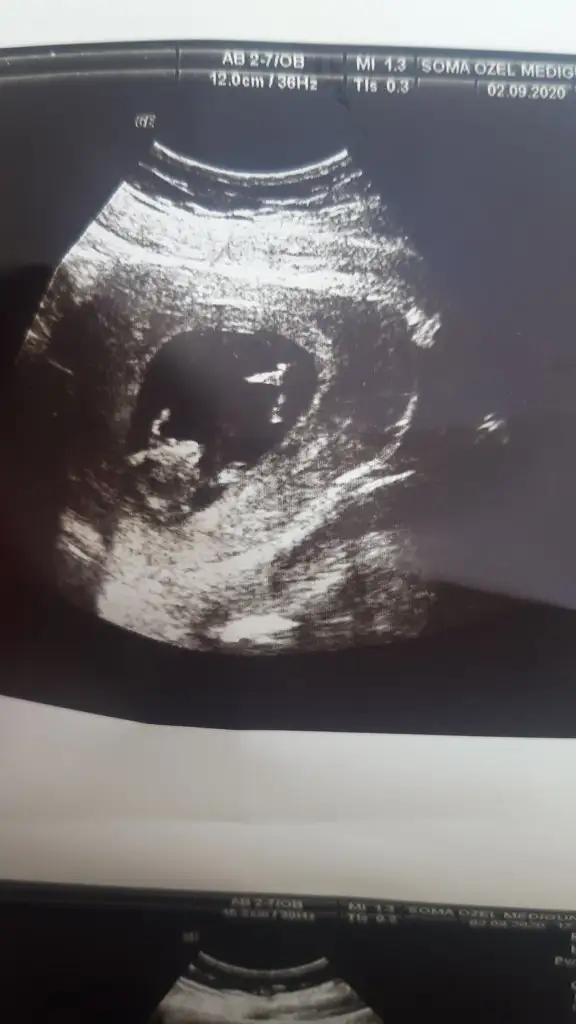

Herkese merhaba en son 9. Haftayı buraya attığımda kız demiştiIkra meyra

Şimdi 12 hafta 1 günlük olduk çok şükür sağlıklı.

Şuan tahmin alabilirmiyim lütfen☺

Sanki yine kız gibiHerkese merhaba en son 9. Haftayı buraya attığımda kız demiştiIkra meyra